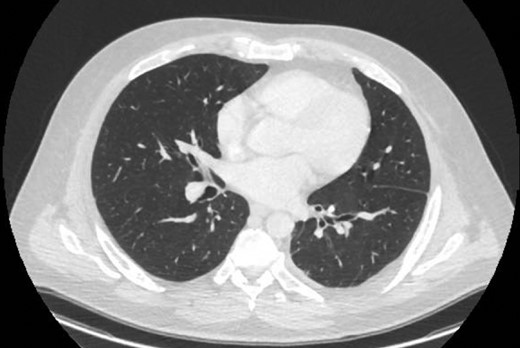

An Intercostal drain was inserted under CT-guidance aiming to decompress the pleural space. Amylase level in the pleural drainage was 880 U/l, Lipase 472 U/l. There was significant reduction of the Hydropneumothorax (Fig. 5). Given his young age, potential for loss of lung volume and infection he proceeded to decortication.

Sagittal view CT Chest post-intercostal catheter drainage of the Pancreatico-pleural fistula. Smaller residual space can be noted compared to Image 3, with some ongoing loss of lung volume and small fluid collection.